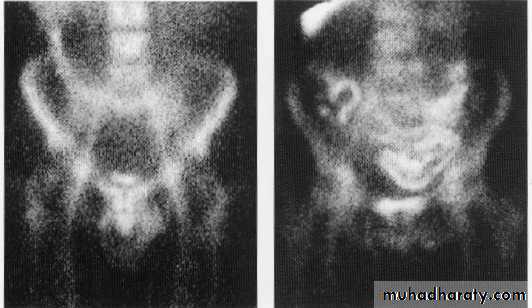

Isotope study of chrons